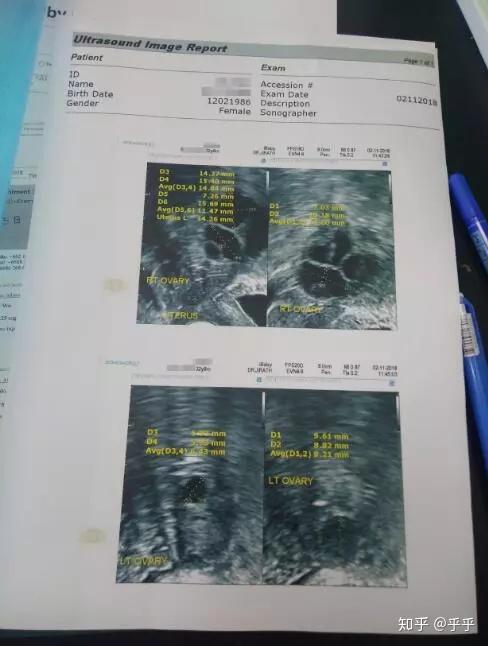

医生给我检查了阴超和激素六项,做检查的时候,出神儿的想到自己居然在国外医院躺着,看着外国人在给我检查,那感觉有些不真实,但要宝宝的期待却又分外的真实!

之前我说过一些我的情况,我是先天性的子宫发育不良,就是俗称的幼稚子宫,这么多年来我都没有月经,年不经事的时候还觉得是个好事,可真到了生宝宝这事,就是横在我和宝宝之前的天堑,哎。

约定的是早晨10点去医院见医生,虽然我听不懂医生说的什么意思,但是看到医生的神态轻松,感觉应该不会有太坏的结果,直到听翻译说,检查结果还是很理想的时候,我算长舒一口气。

之前医生建议我选择P23,我还担心卵子技术不够,之前检查出的结果是卵子数量只有9个。

今天去医院取卵,大大小小有18个!是之前检查显示的两倍!!哈哈哈哈,这个是我们之前没想过的,太高兴了,简直就是一个大惊喜。